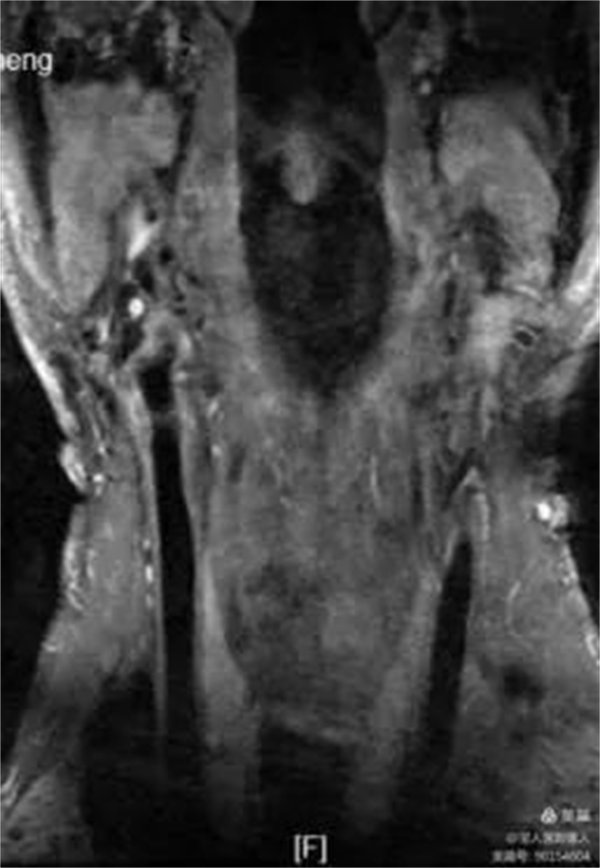

67岁男性,颈动脉斑块成像显示:颈总动脉及颈内动脉粥样斑块,偏心性生长伴出血,MRI诊断不稳定性斑块。

冠状位显示颈内动脉起始段管壁增厚,呈高信号

增强明确管壁增厚原因

平扫和增强对比明确管壁增厚病因,提示:粥样斑块,并内出血,多系不稳定斑块